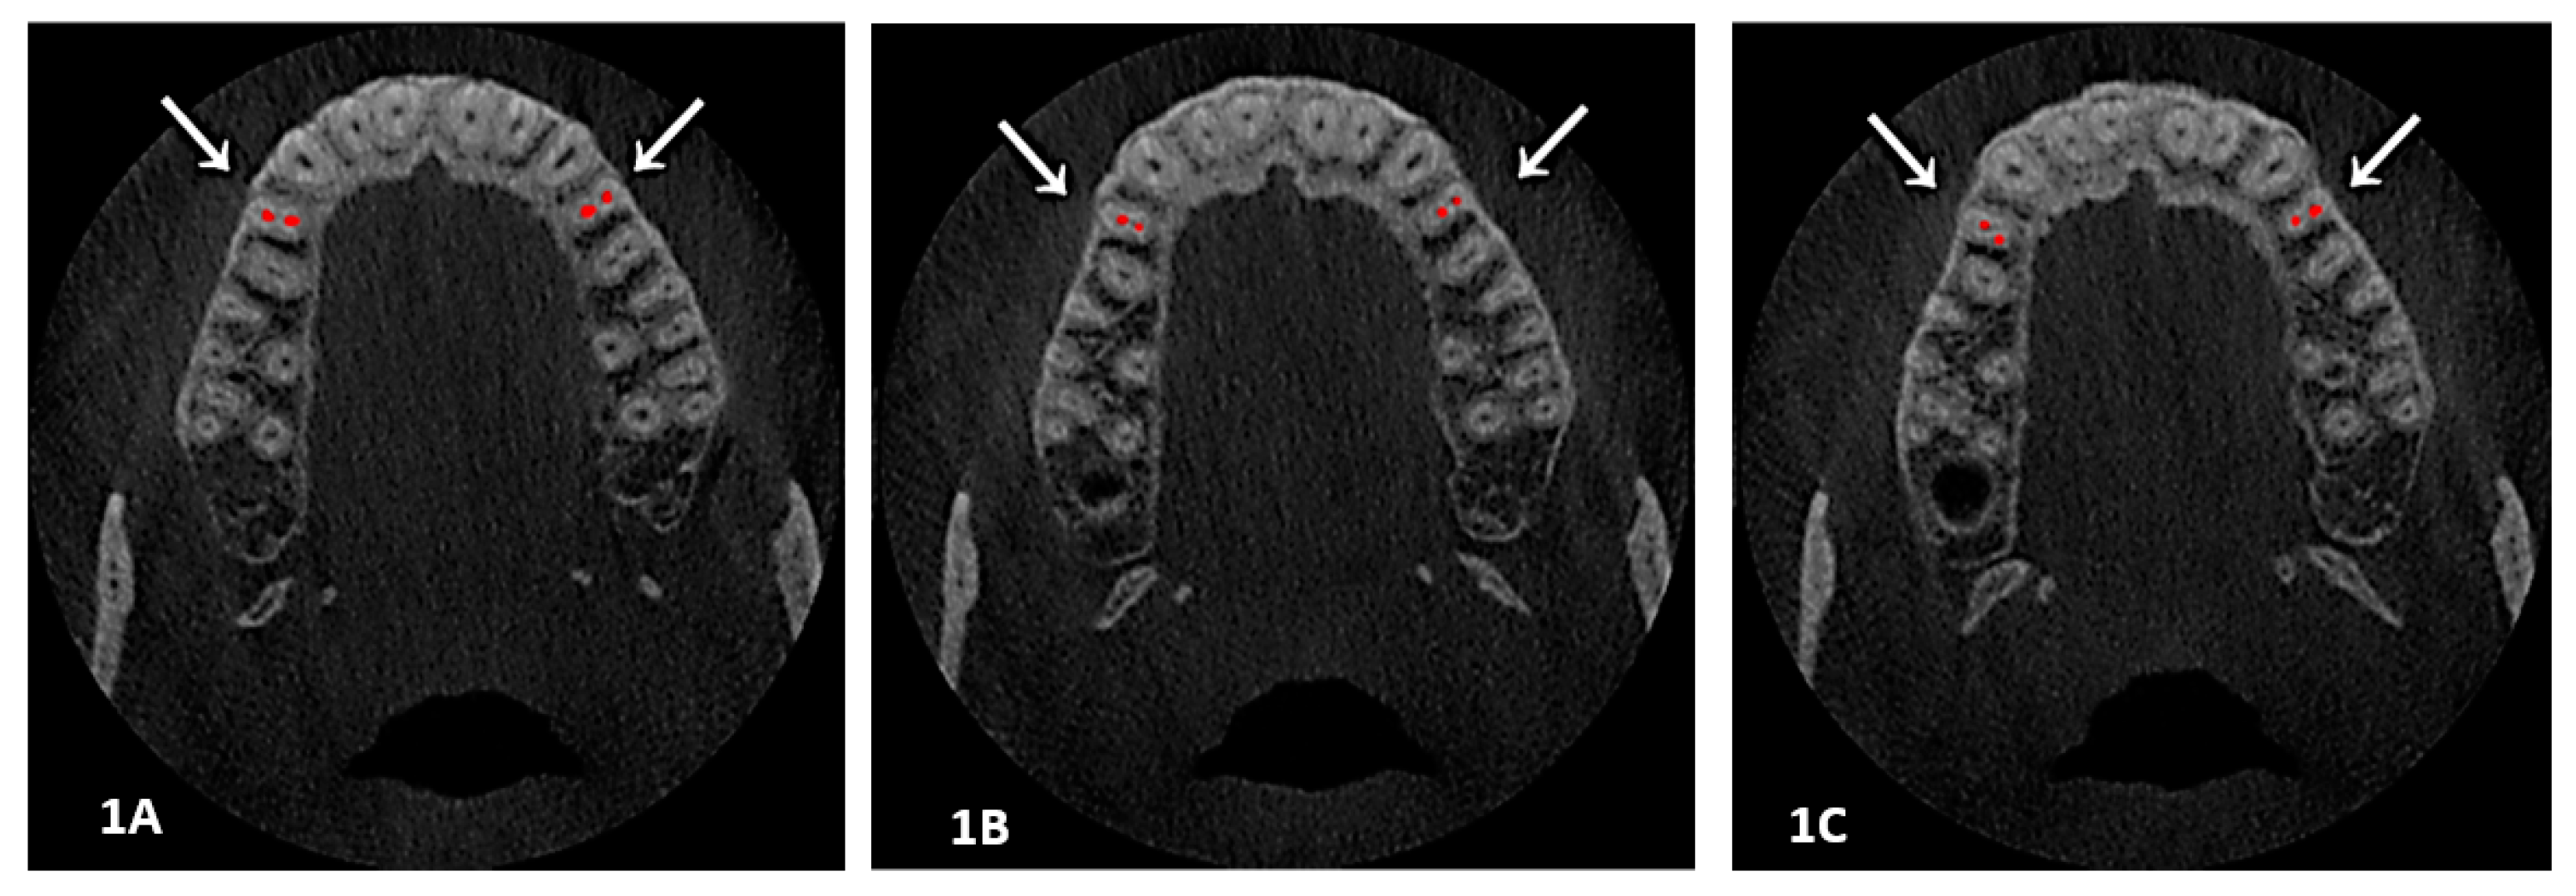

Two sections (axial and sagittal views) of each CBCT image with a significant number of slices were analyzed. The root canal tracing using an Axial view helped in studying root canal morphology in respect to Ahmed’s classification from the orifice to the foramen, course and number of canals at three levels: orifice, coronal third of root and portal of exit. Furthermore, the sagittal view was used for detecting a root canal configuration and applying Vertucci’s patterns (see Figure 1A–C and Figure 2).

Figure 1.

(1A, 1B and 1C): An axial view showed a root canal system at different levels; here is an example of two canals with two foramen at three levels, Section (1A) at orifice, while Section (1B) is at the coronal-middle third, and Section (1C) is at the foramen level. Classification codes came as Vertucci IV, 2 FP B1 P1.